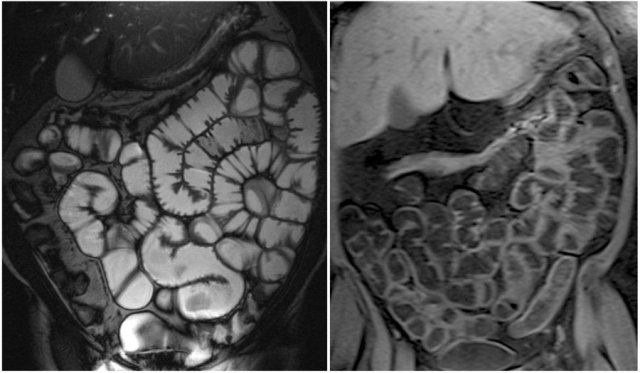

Here we see a coronal T2W-image and a coronal T1W-image with fatsat.

Notice that the small bowel is well distended.

Luminal distension should be ≥ 2 cm.

Bowel wall thickness > 3 mm is considered abnormal.

Collapsed small bowel loops can be easily misinterpreted as wall thickening or abnormal enhancement.

On the coronal T1W-image the jejunal loops are collapsed.

As a result it looks as if there is bowel wall thickening and prominant enhancement.

On the T2W-image during the same examination there is normal distention.